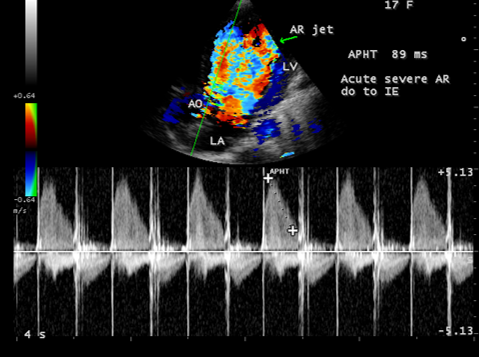

A 17-year-old female was brought to the emergency room with a history of sudden onset of breathlessness. Her pulse rate was 87 bpm and blood pressure 110/60 mmHg. She had a history of rheumatic fever during childhood, an episode of febrile illness for 10 days and taken antibiotic treatment recently. Blood chemistry revealed normal and blood cultures were negative. ECG revealed normal as shown in Figure 1 and X-ray chest revealed dilated LV (left ventricle) as in Figure 2. Physical examination revealed grade 3/6 early diastolic murmur over left mid sternal border, basal crackles over lung fields and no peripheral signs of wide pulse pressure. Transthoracic echocardiography revealed vegetations on anterior and posterior leaflets of aortic valve as in Figure 3 and Figure 4, with a “kissing-type “as in Figures 5, 6 and 8. The aortic valve was bicuspid with an attached vegetation as in Figure 9 and it was severely regurgitant as in Figure 10 and Figure 11. The left ventricle is dilated as in Figure 12 with moderate LV dysfunction as in Figure 13. The thoracic aorta was prominent as in Figure 14 with a ‘holodiastolic flow reversal’ as in Figure 15. The patient was treated with digoxin (0.25 mg, half daily), diuretics (Injection. Furosemide 20 mg IV twice daily), ACE inhibitors (tablet. Enalapril 2.5 mg twice daily) along with 2 weeks course of intravenous (IV) cefotaxime (1g) and amickacin (500mg) twice daily and advised aortic valve replacement at the earliest with lifelong penicillin prophylaxis and continuation of antibiotics for 6 weeks since the vegetations remain stable after 2 weeks of treatment, but without any embolic episodes.

masses with atypical location. Transthoracic echocardiography detects 70% of vegetations > 6 mm and 25% of vegetation < 5>Figures 3 to 9. When endocarditis involves the aortic leaflets, the resultant acute, severe regurgitation as shown in Figures 10, 11 and 15, may often causes dilated left ventricle as in Figure 12 and a prominent aorta as in Figure 14. Secondary infection of mitral valve is a possible finding in primary aortic valve endocarditis. Large aortic valve vegetations (> 6 mm) prolapse into the left ventricular outflow tract and “kiss” the ventricular surface of the anterior mitral leaflet with the development of a vegetation [27],[28],[29]. The left ventricular outflow tract endocarditis may represent the initial site of infection with a possibility to spread by contiguity to both left-sided valves, the mitral and aortic [30], causes the “mitral-kissing vegetation” with a higher prevalence of embolic events [31].

Since the patient had a bicuspid aortic valve as shown in Figure 9 and a history of rheumatic fever during childhood, rheumatic inflammation occurred on the aortic valve and harboured the infective vegetation through the vascular access during the treatment of febrile episodes. Patients with infective endocarditis are at risk of developing acute aortic regurgitation and the ECG can appear normal as in Figure 1 and the chest X-ray usually shows pulmonary edema with normal heart size. A dilated left ventricular cavity with a normal left atrium as in Figure 12 indicates that the volume overload on the left ventricle resulted a compensatory mechanism to maintain an adequate forward stroke volume by accomodating a large regurgitant fraction without an increase in end-diastolic pressure. The heart rate appeared normal (87 bpm) as the result of this compensation. Even though the aortic regurgitation is acute as in Figure 10 which showed a steep deceleration slope with a narrow width of regurgitant jet due to endocarditic lesion of aortic valve (endocarditic regurgitation). It is compensated in this patient and showed a lesser degree of decompensation as moderate LV dysfunction with an ejection fraction of 42% as in Figure 13, necessitating elective aortic valve replacement along with removal of vegetations with a mechanical prosthetic valve. Anticoagulation with warfarin to maintain the INR (international normailised ratio) between 2 to 3 is indicated after the clearance of active stage of endocarditis with antibiotic therapy and surgery.